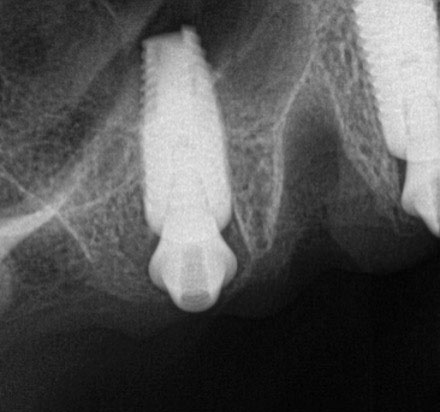

Fig 11. Initial panoramic radiograph.

Figure 11

A 60-year-old female patient presented with many periodontally and restoratively hopeless teeth that severely compromised esthetics and function and were inadequate to retain a maxillary restoration. She declined to advance into a full maxillary denture or partial denture. Existing maxillary teeth included Nos. 2 and 4 through 14 (Figure 9 and Figure 10). The opposing dentition was stable. The patient was in good health with no allergies to medication.

At the initial visit, a panoramic x-ray (Figure 11) and periapical x-rays were taken. The patient was photographed to capture her full face and shoulders, and a digital scan of the maxillary dentition was obtained. This file was electronically sent to the implant company to complete the VSD.